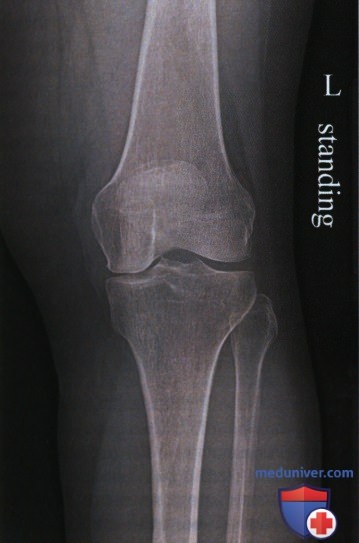

Рекурвация коленного сустава: рентгеновские снимки и объяснения